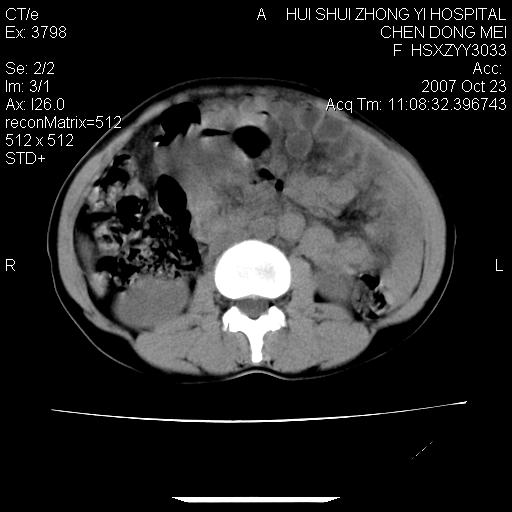

腹腔巨大软组织密度影,边缘光滑,包膜完整,内囊变坏死。腹膜后及盆腔内淋巴结肿大。结合病史考虑卵巢癌可能性大。

病变巨大,呈囊实性改变,包膜较厚且完整,内见分膈,周围脏器明显受压移位,病变与左侧附件关系密切,考虑来源左侧附件的囊腺瘤,不除外癌变可能;畸胎瘤可能性较小。

病变巨大,呈囊实性改变,包膜较厚且完整,内见分膈,周围脏器明显受压移位,病变与左侧附件关系密切,考虑来源左侧附件的囊腺瘤,盆腔内见肿大淋巴结,不除外癌变可能。

病变巨大,呈囊实性改变,包膜较厚且完整,内见分膈,周围脏器明显受压移位,病变与左侧附件关系密切,考虑来源左侧附件的囊腺瘤,不除外癌变可能

腹膜后可见肿大的淋巴结,卵巢囊腺癌可能性大